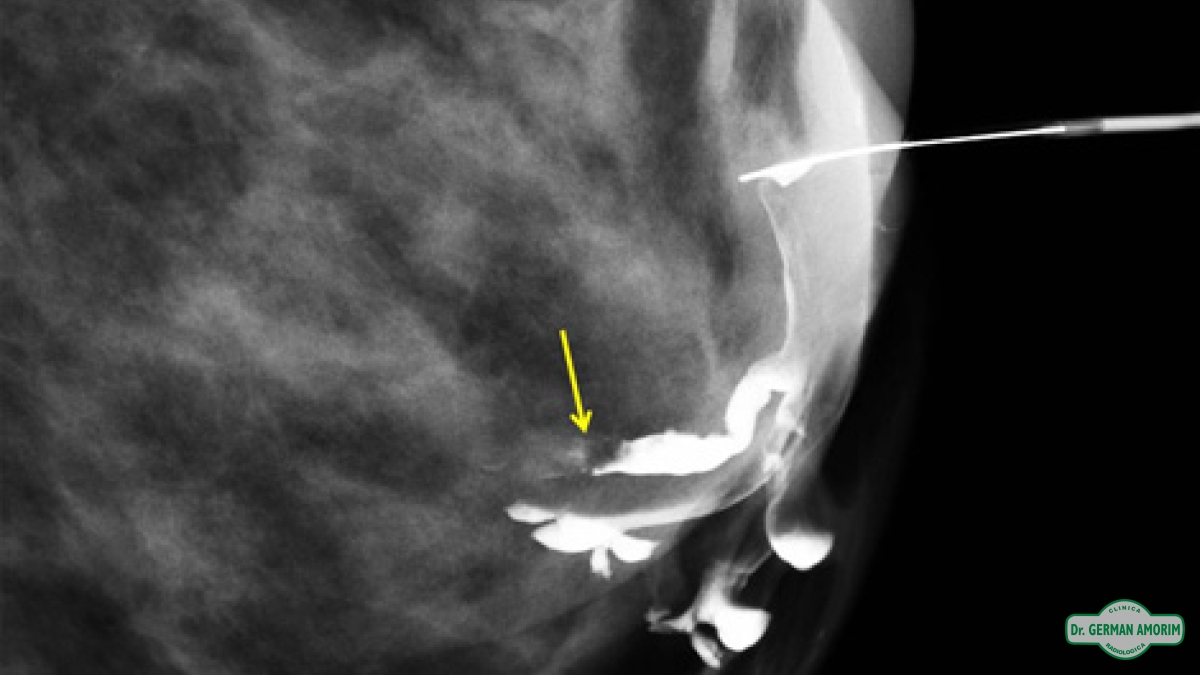

Galactografía

La galactografía es uno de los procedimientos intervencionistas de la mama que consiste en la realización de mamografías tras la administración de contraste radiopaco a través de un orificio en el pezón.

La lesión intraductal más frecuente es el papiloma y aunque el carcinoma intraductal tiene una frecuencia menor, al no poder distinguir entre ellas con este método de imagen, se recomienda la escisión quirúrgica. Es en este contexto que la galactografía sirve de mapa prequirúrgico para identificar correctamente el conducto patológico, la extensión de la lesión intraductal y la posible existencia de lesiones múltiples.

Entre las ventajas de esta técnica de imagen podemos mencionar la alta capacidad de definición de los ductos y de las posibles lesiones intraductales tras la administración de contraste, permitiendo así un mapa prequirúrgico para una escisión lo más selectiva posible.